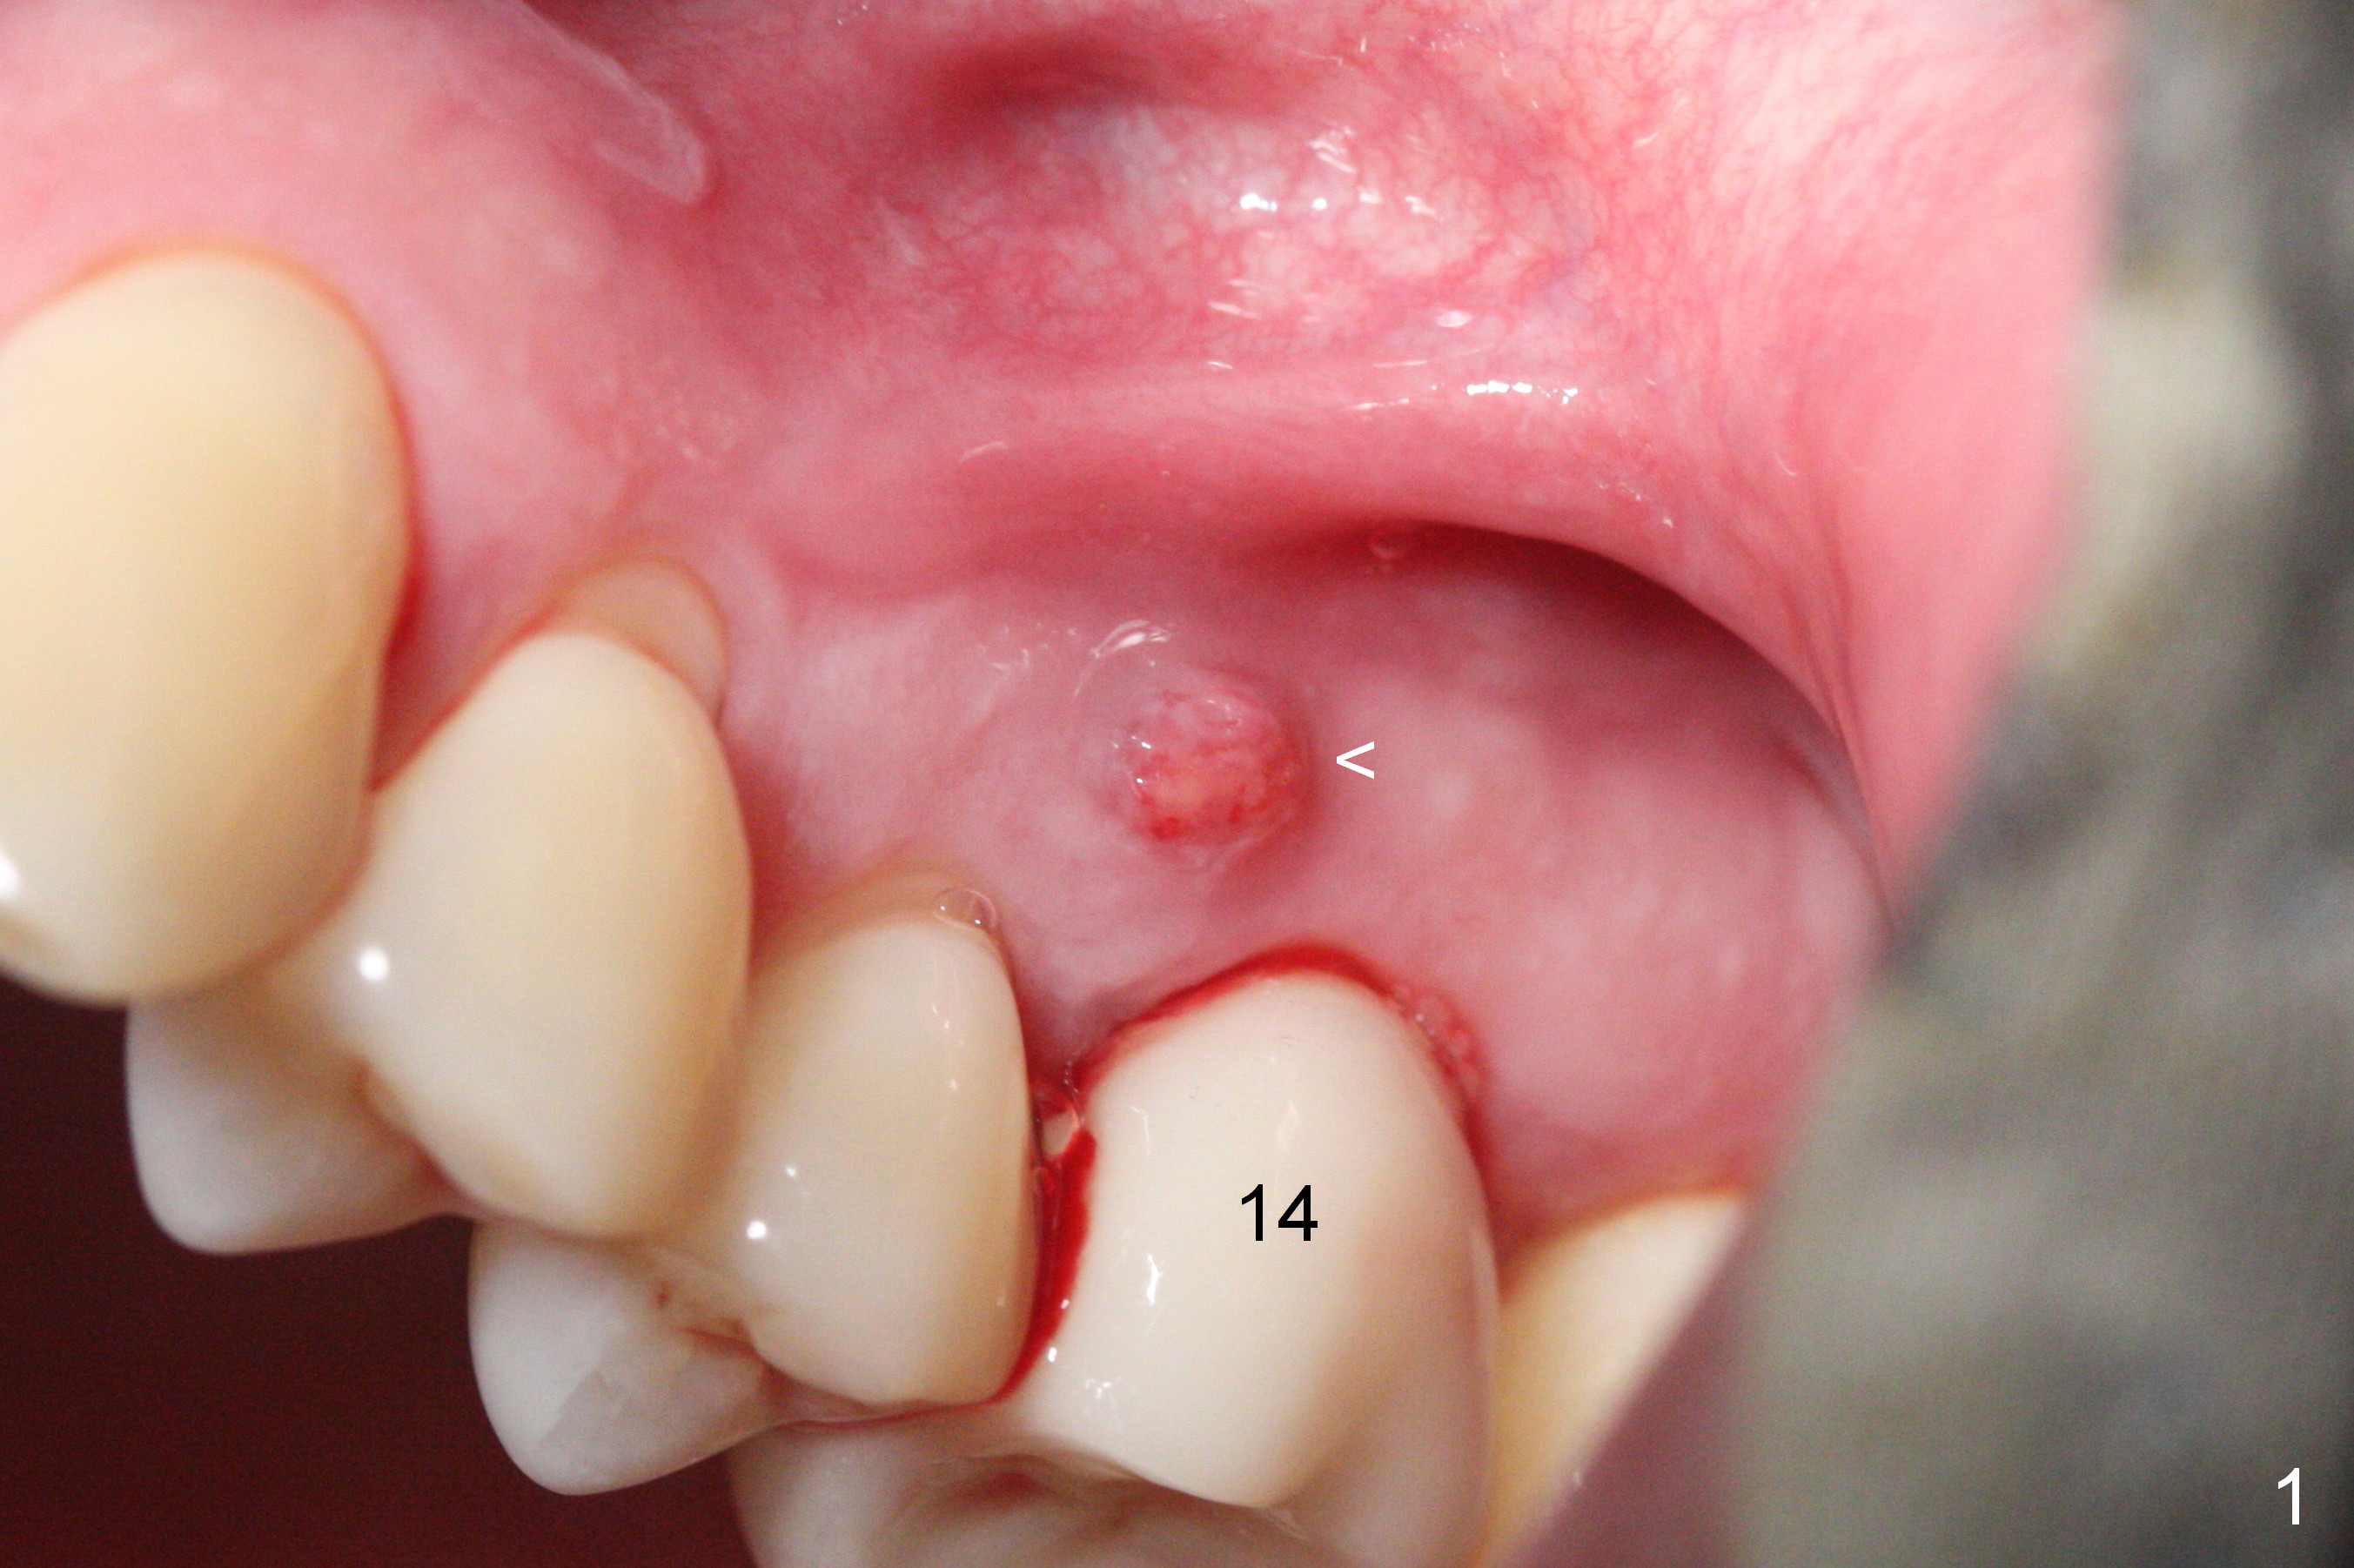

There is purulent discharge from the mesiobuccal fistula (Fig.1 <) during the tooth #14 extraction. Fig.2 is a coronal section of CBCT of the affected tooth showing a large apical lesion (*). When the tooth is removed (Fig.3), limited amount of granulation tissue is removed apical to the palatal root (P in Fig.2). The granulation tissue (Fig.4 red area) above the septum (Fig.3 S) is thoroughly extirpated when the septum is removed (Fig.5 black area).